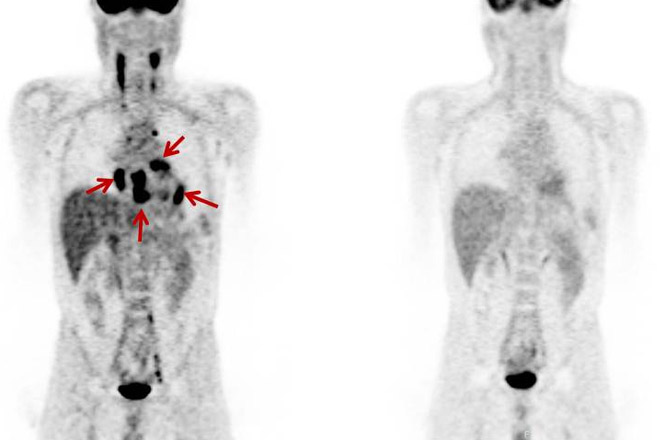

Figure 2:完全房室ブロックを来たした心サルコイドーシス

心臓に関しては、左室心筋前壁、側壁、中隔、右室心筋前壁、心尖、右房相当部位に集積を認めた(左図)。

ステロイド加療後は心筋への異常集積は消失している(右図)。